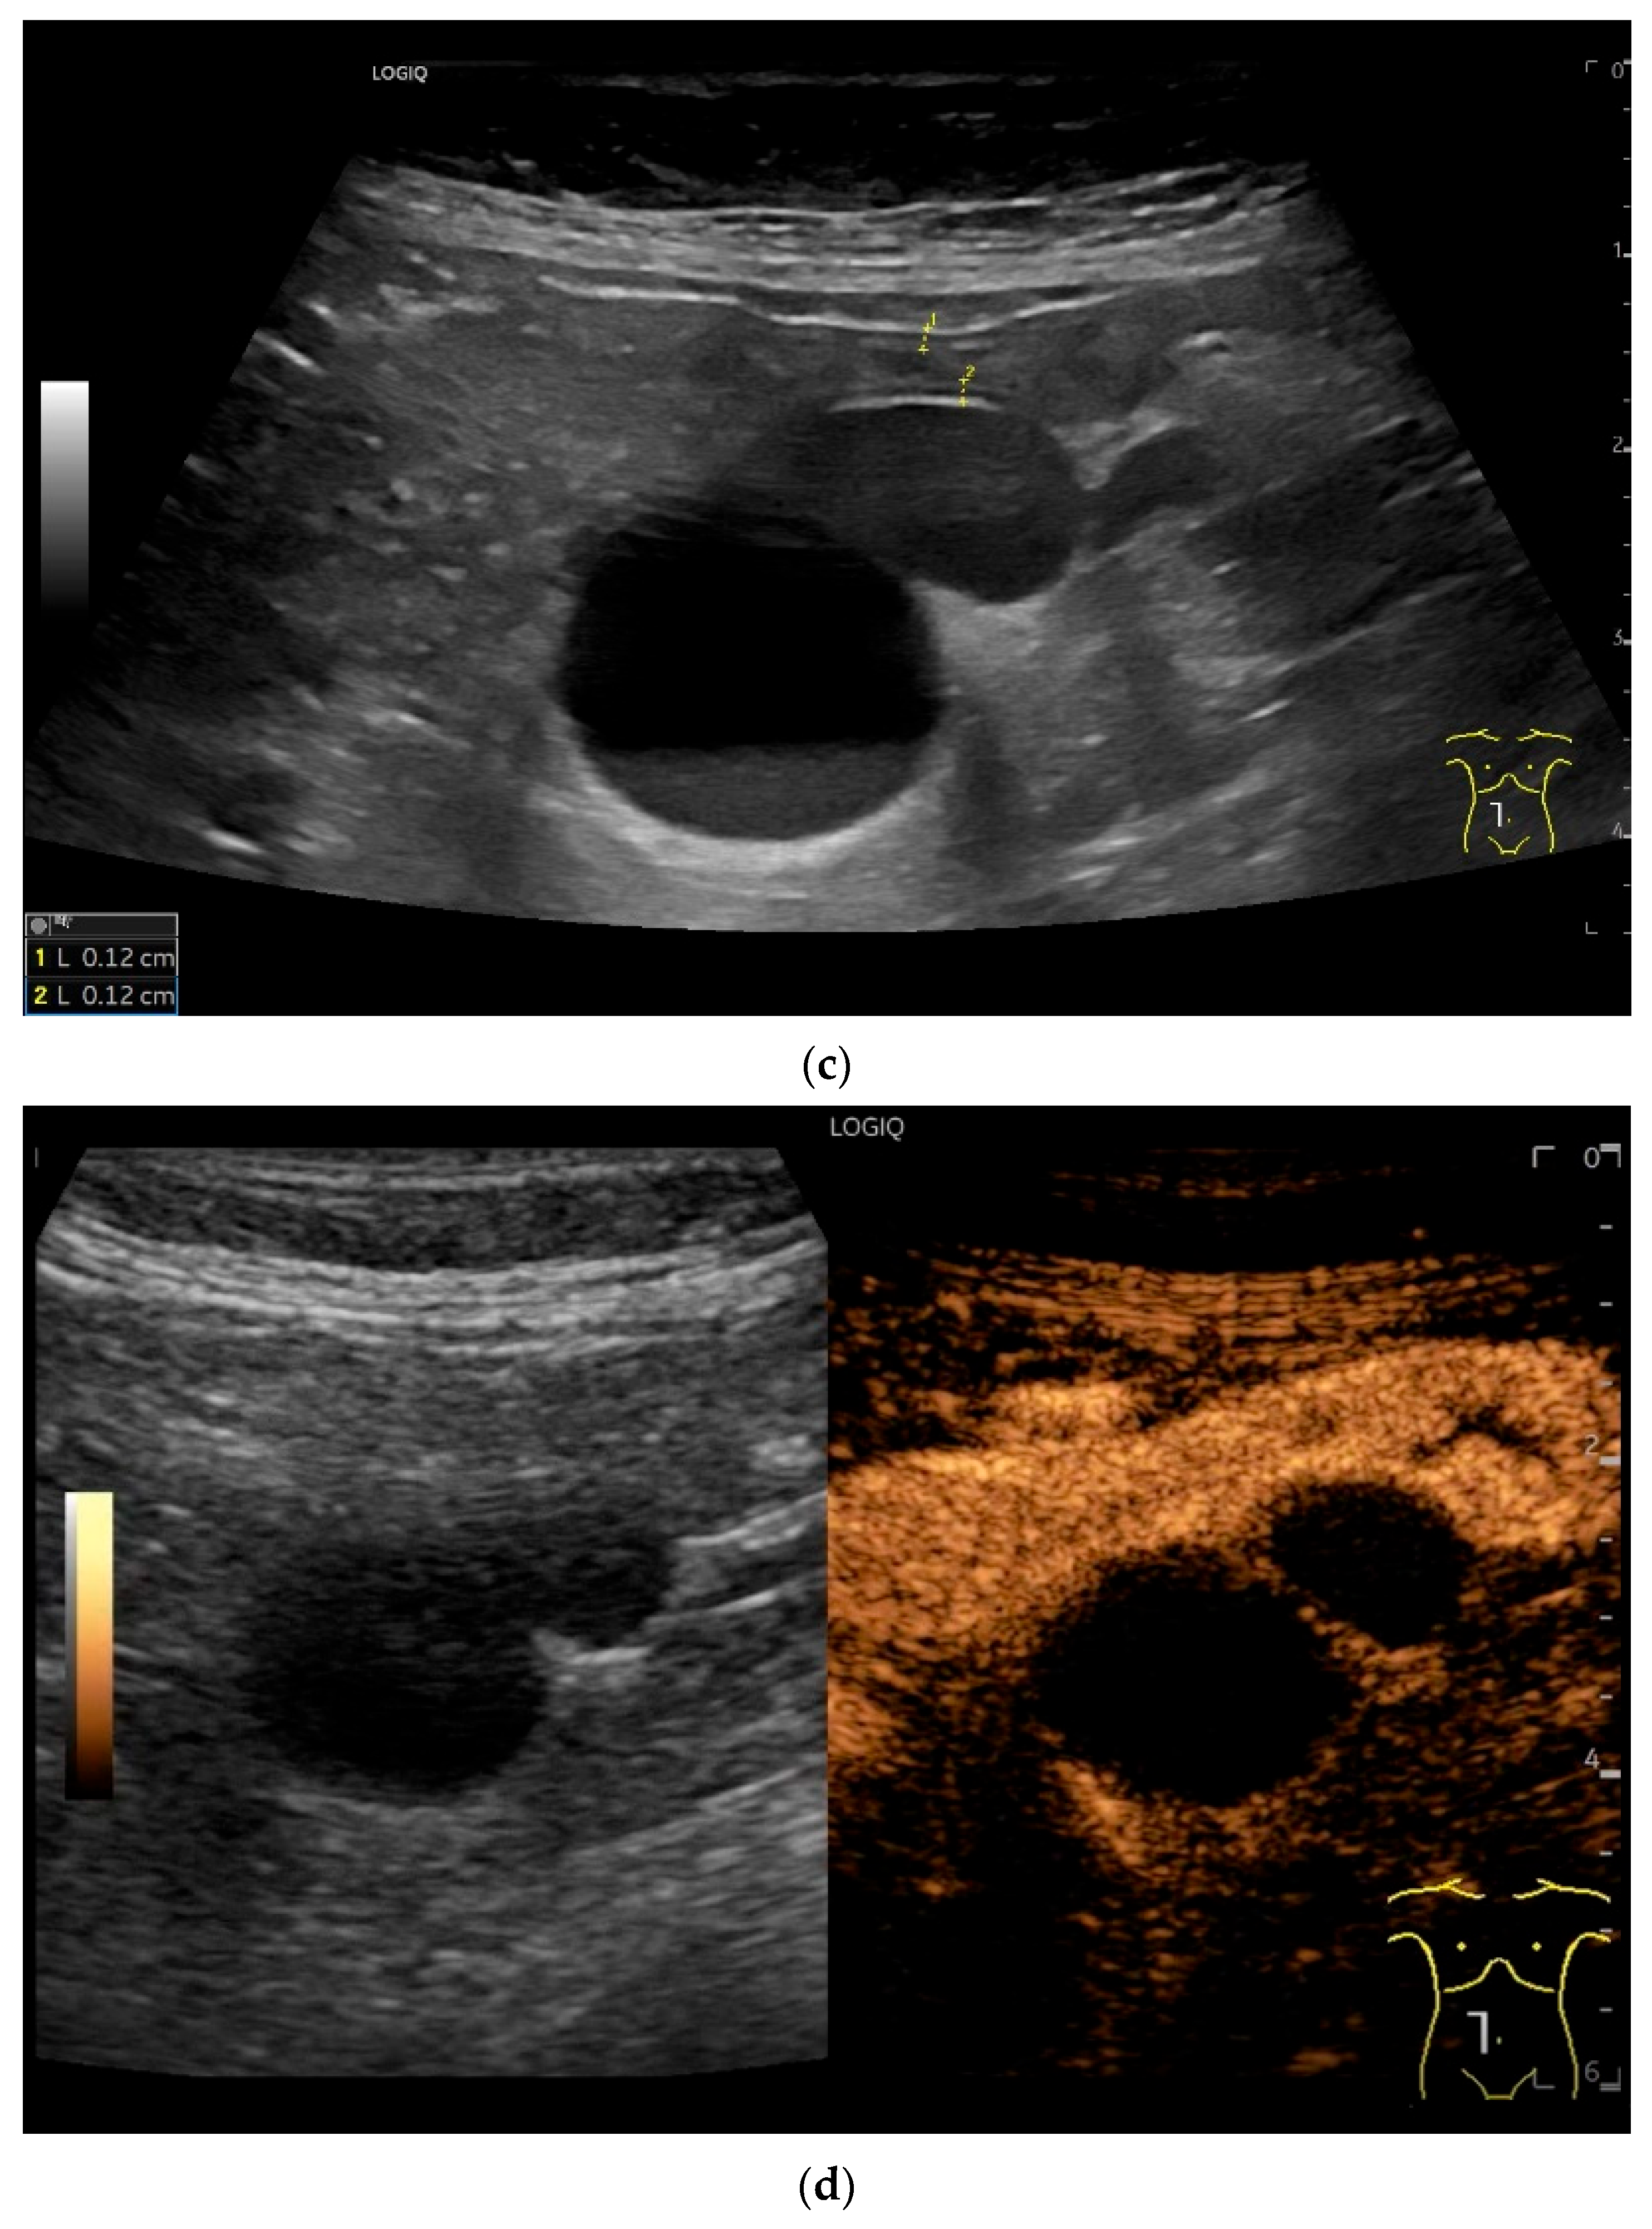

Figure 11.

GIST. A 30 mm large, very hypoechoic, almost anechoic round mass is visible in the left upper abdomen. This is located in the jejunum; the wall (W) and lumen (L) are visible (a). Macro vessels can be distinguished on Power Doppler, demonstrating that the lesion is solid and not cystic (b). On CEUS with 2.4 mL SonoVue (linear transducer 9 MHz), a small wheel-spoke-like vascular branching is visible at the margin (arrow) (c) with centrifugal enhancement (arrow) (d). Hyperenhancement is heterogeneous in the early arterial phase (e,f) and becomes homogeneous in the later course of the arterial phase (g). The extent of the heterogeneously enhanced tumor is marked with arrows (e). The intensity of the enhancement decreases during the first minute. The tumor is marked with arrows (h). Jejunal segment resection revealed the histology of an epithelioid GIST.

Figure 12.

GIST. Incidental finding of a 35 mm, slightly polycyclic, homogeneous hypoechoic mass in the left upper abdomen (a,b). This changes position with the movements of the small intestine. In CEUS with 1.2 mL SonoVue using the abdominal sector transducer (1–5 MHz), the mass shows homogeneous hyperenhancement in the arterial phase (c). The intensity then decreases (d). The tumor is marked with arrows in CEUS.